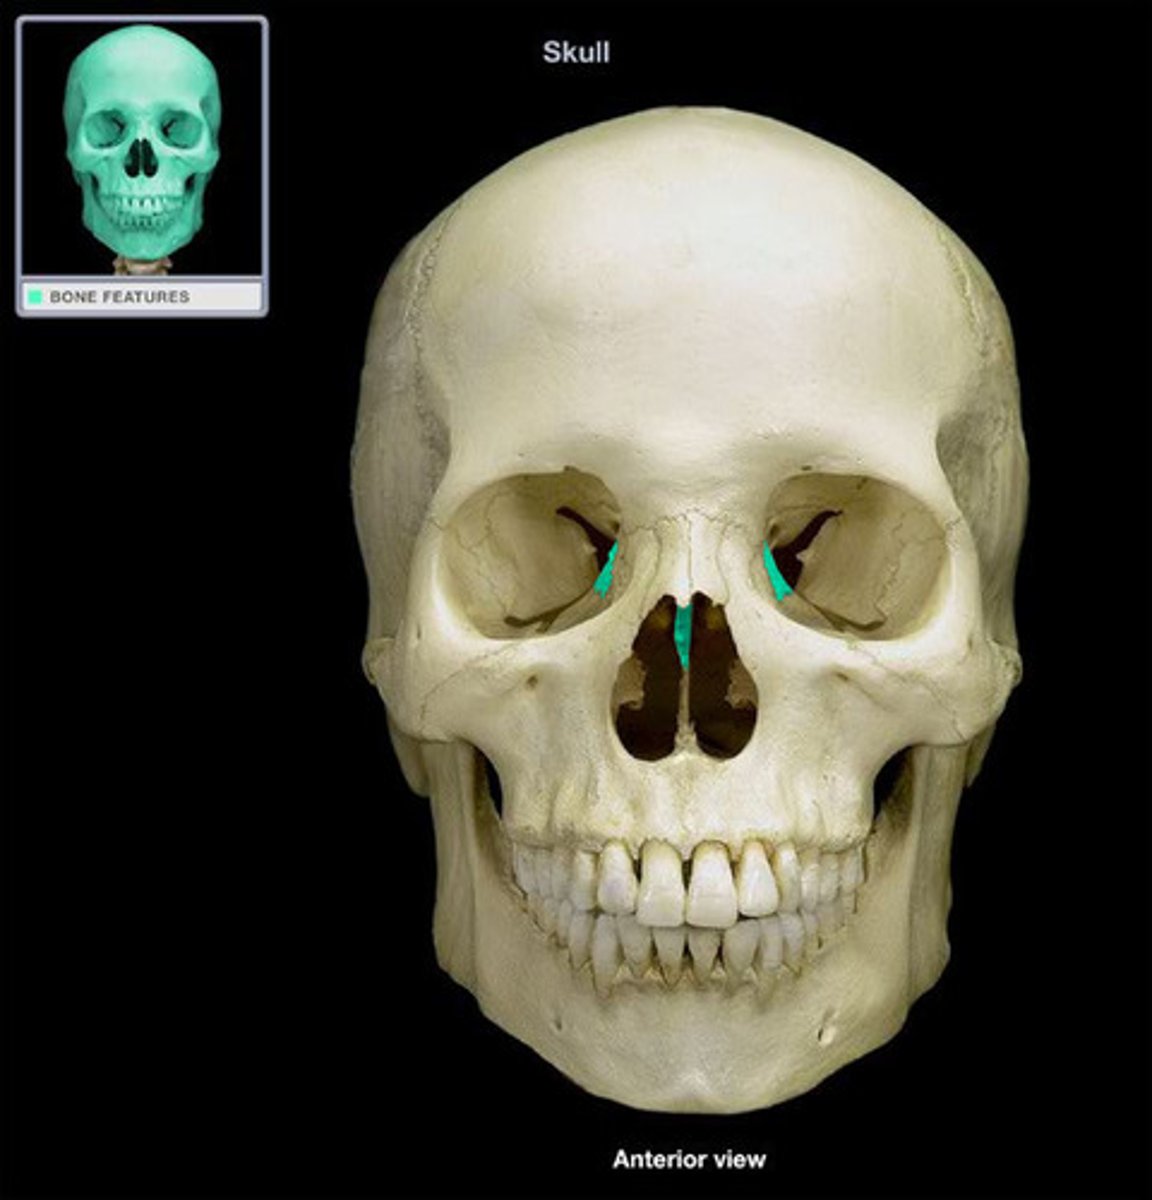

Lacrimal Bone

Vomer

Vomer